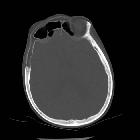

CT

Bony changes are largely identical to those depicted in radiographic findings. Attenuation values of bone marrow space in affected areas are often those of macroscopic fat.

As Paget disease most often presents as a continuum rather than distinct phase, sclerotic areas of the blastic (mixed) phase may more readily be detected. They usually present as cortical and trabecular thickening in a disorganized pattern without bony destruction.